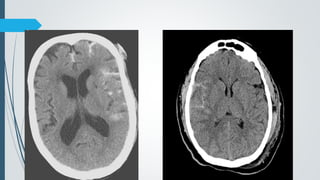

Age of SDH

CT Findings

 Hyperacute

 Heterogenous or hypodense

 Acute

 60% homogenously hyperdense

 40% mixed hyper-, hypodense with active bleeding (Swirl sign)

 Subacute

 Iso to hypodense

 GM-WM junction displaced medially

 Progression from hyper to iso to hypodense over nearly 3 weeks.

Acute SubacuteAcute

Chronic Acute on chronic